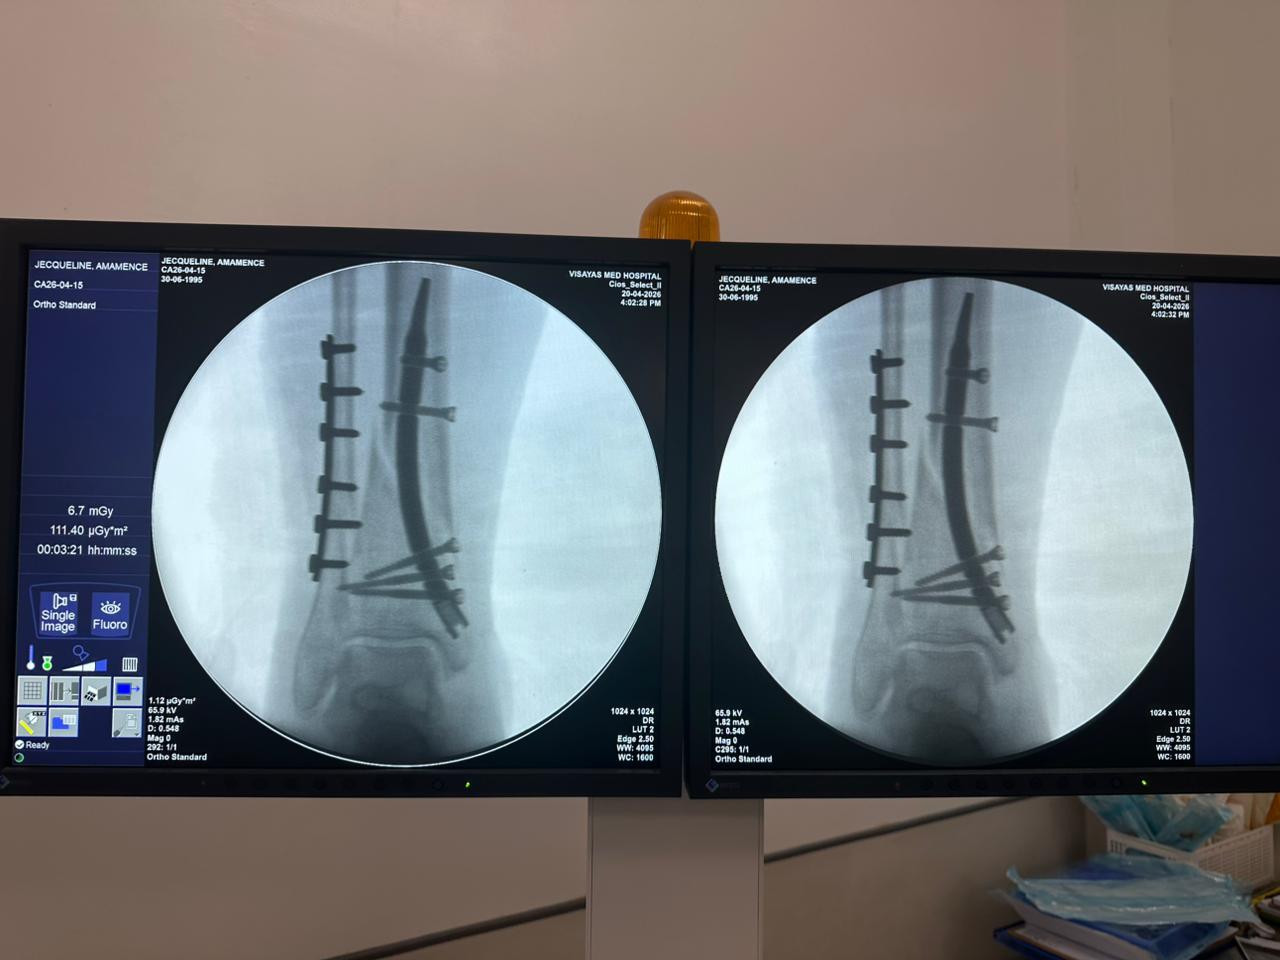

Étude de cas sur la fixation d'un clou tibial distal avec support de plaque fibulaire

Radioscopie peropératoire de l'arceau, vues AP et latérales

Ce cas concernait une fixation tibiale distale à l’aide d’un clou tibial distal intramédullaire. La radioscopie peropératoire a confirmé la position du clou, des vis de verrouillage distales et de la fixation par plaque fibulaire.